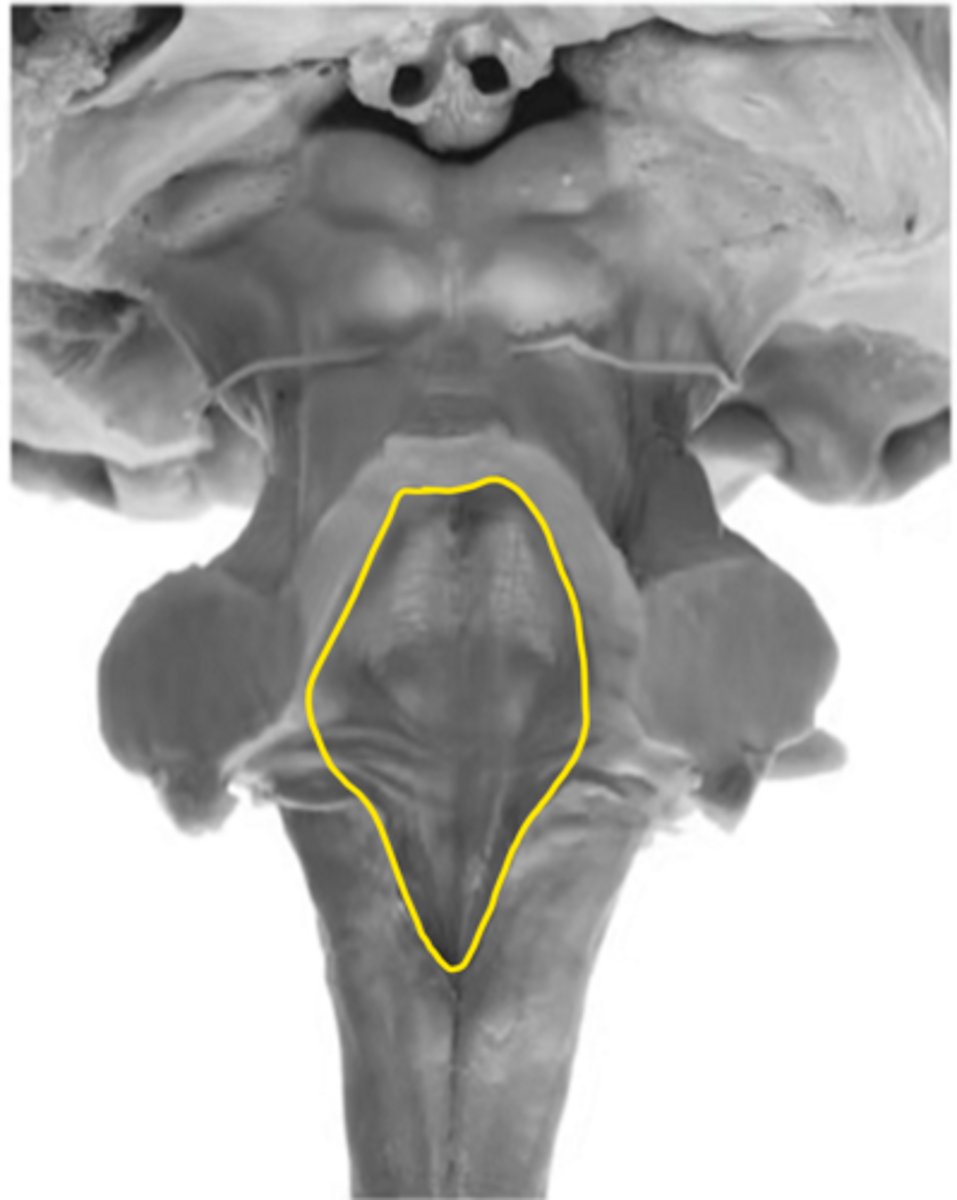

fourth ventricle

ID the space

foramen of Luschka